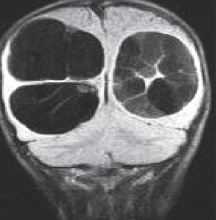

МРТ головного мозга. Т2-взвешенная корональная МРТ. Киста кармана Ратке.

Киста кармана Ратке представляет собой редко встречающееся образование из остатков эмбриональной эктодермы (щель Ратке), расположенное между долями гипофиза. Выявляется в любом возрасте, но чаще в 50-60 лет. Клинические проявления связаны с масс-эффектом. При МРТ головного мозга выявляется небольшая (3-5мм) киста с четким контуром, без отека вокруг, однородная по структуре. Сигнал на МРТ головного мозга зависит от содержимого. При серозном содержимом сигнал типично жидкостный, при мукоидном киста светлая на Т1-взвешенных МРТ головного мозга. В 70-80% случаев внутри кисты выявляется неконирастирующийся узелок («пятно») - признак патогномоничный для кисты кармана Ратке. В редких случаях киста достигает больших размеров и даже выходит за пределы седла. Стенка кисты иногда усиливается при МРТ головного мозга с контрастированием. Дифференциальная диагностика при МРТ головного мозга должна проводиться с арахноидадьной и эпидермоидной кистами, тератомой, кистозной аденомой гипофиза и краниофарингиомой. Иногда при МРТ головного мозга киста кармана Ратке напоминает “пустое” турецкое седло. При маленьких размерах кисты ее на до дифференцировать на МРТ с микроаденомой гипофиза.